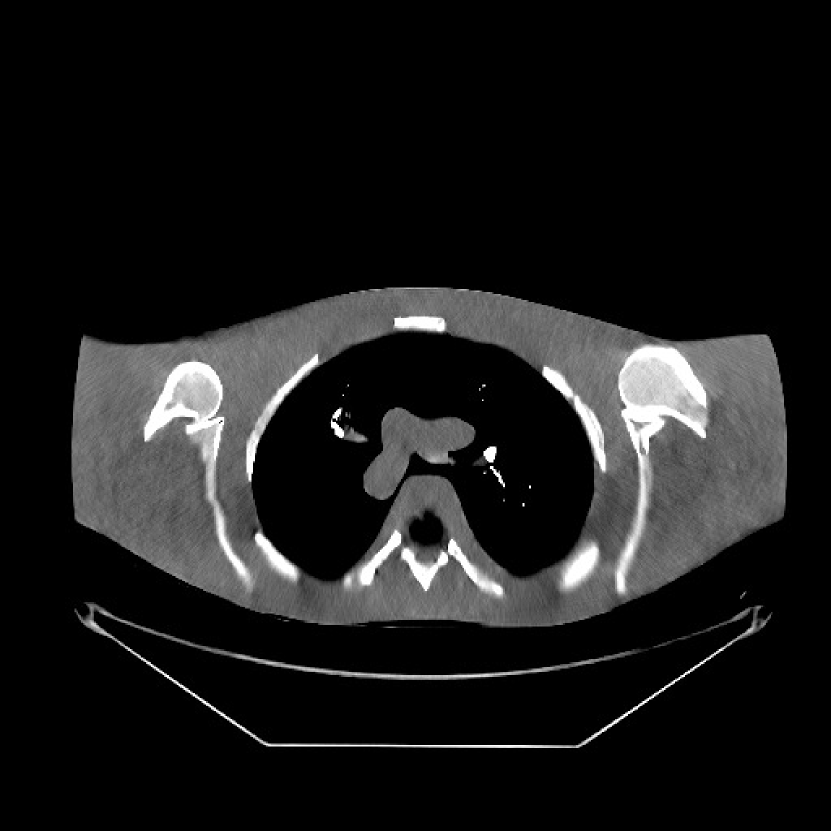

Fig. 9 shows three axial slices from the 3D reconstructions with SPULTRA and PWLS-ULTRA at : the middle slice (No. 67) and two slices located farther away from the center (No. 90 and No. 120). The image profiles along a horizontal line (shown in green) in the displayed slices are also shown in Fig. 9. The reconstructed slices using PWLS-ULTRA appear darker around the center compared to the “true” clinical image and the reconstructions with SPULTRA. This means PWLS-ULTRA produces a strong bias in the reconstruction. The bias can be observed more clearly in the profile plots: the pixel intensities for the SPULTRA reconstruction better follow those of the “true” clinical image, while those for the PWLS-ULTRA reconstruction are much worse than the “true” values. Moreover, SPULTRA achieves sharper rising and failing edges compared to PWLS-ULTRA. In other words, SPULTRA also achieves better resolution than PWLS-ULTRA. Fig. 9 also shows a zoomed-in ROI for each of the chosen slices, and highlights some small details with arrows. It is clear that in addition to reducing the bias, SPULTRA reconstructs image details better than PWLS-ULTRA.